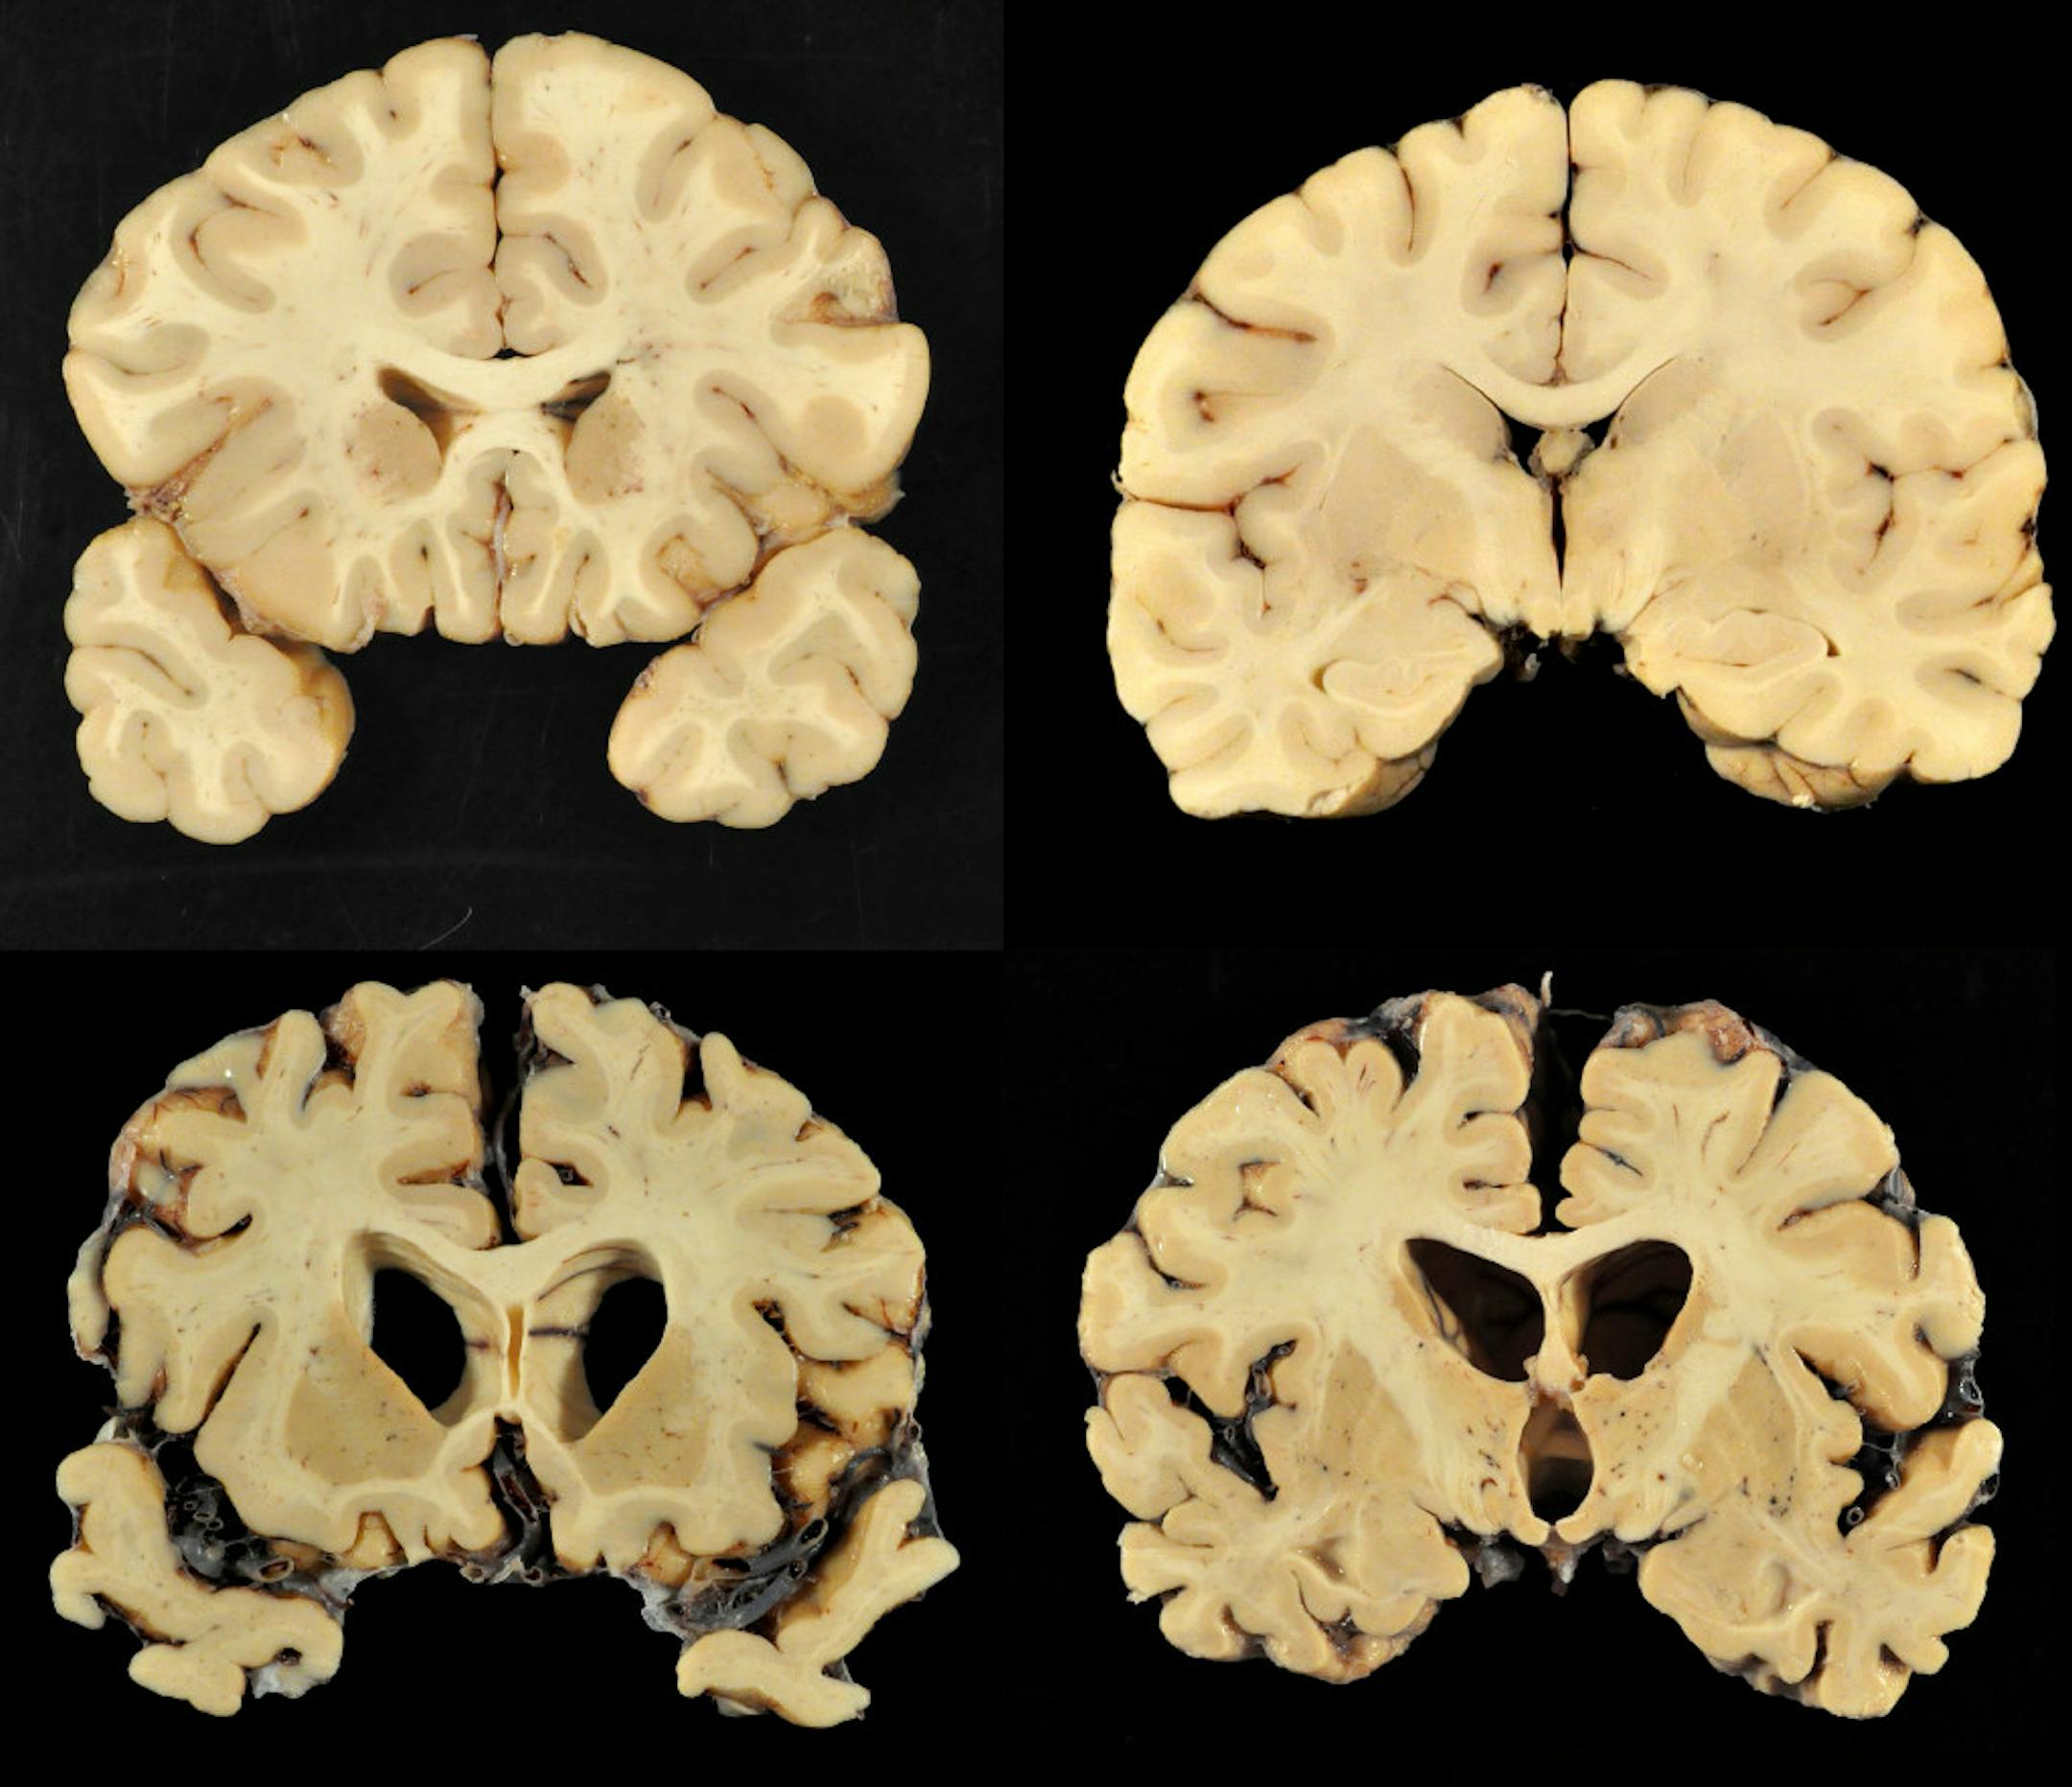

The brains of 111 deceased former NFL players were studied, and 110 of them — yes, all but one — had evidence of CTE. The study was published in The Journal of the American Medical Association.

Per the New York Times: The brains here are from players who died as young as 23 and as old as 89. And they are from every position on the field — quarterbacks, running backs and linebackers, and even a place-kicker and a punter. They are from players you have never heard of and players, like Ken Stabler, who are enshrined in the Hall of Fame. Some of the brains cannot be publicly identified, per the families' wishes.